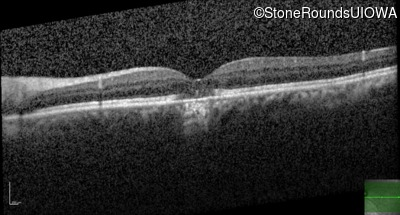

Optical Coherence Tomography - Right - 20/20 +2

Exemplar / OCT Stack

OCT Stack